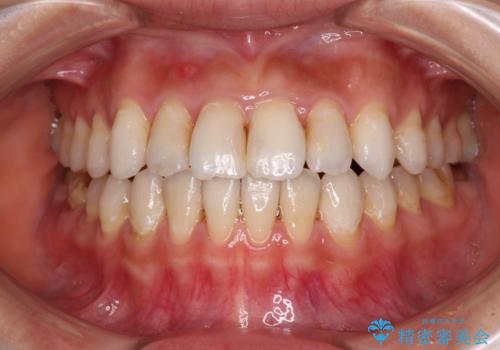

【モニター】開咬を治したい インビザラインによる矯正治療

- 上下前歯の開咬とデコボコを気にして来院された患者様です。

開咬(オープンバイト)はインビザラインによる矯正治療がワイヤー装置と比べて圧倒的に有利であるため、インビザラインによる矯正治療を行うこととしました。

通院されなかった時期があって治療期間が長くなったり、奥歯に抜歯が必要な歯があったりと、治療は一筋縄にはいきませんでしたが、何とか治療を終えることができました。